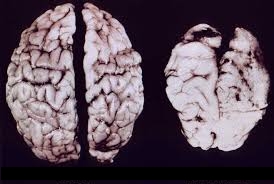

The venality of the Axis of Evil (Psychiatry and Big Pharma) evidently knows no bounds. It has just come to my attention that they have known for AT LEAST THREE YEARS that antipsychotic drugs, the new atypical antipsychotics and clozapine are all associated with loss of brain tissue – in other words, brain damage.

I cite an article that appeared in Psychology Today almost exactly three years ago. The article itself cites an admission by a former editor-in-chief of the American Journal of Psychiatry and findings that were published in the February issue of the Archives of General Psychiatry, that the link between those psychiatric drugs and “progressive brain volume reductions.”